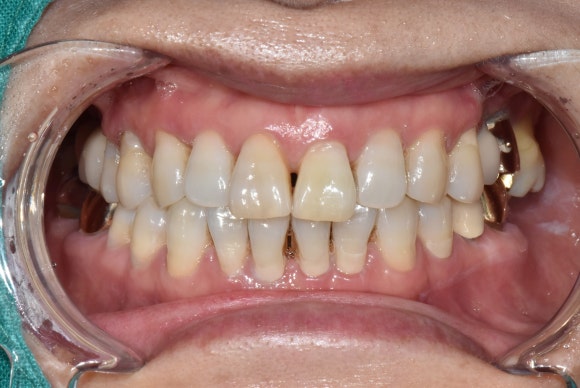

두번째 케이스

왼쪽에 보이는 작은 앞니에 주목해주세요.

이 경우도 마찬가지로 오랜기간 괴사를 겪으면서 짙은 오렌지색으로 변색된 케이스입니다.

마찬가지로 신경치료 후에 미백치료를 시작하였고, 3회차에 치료를 종료하셨습니다.

치료 전 후